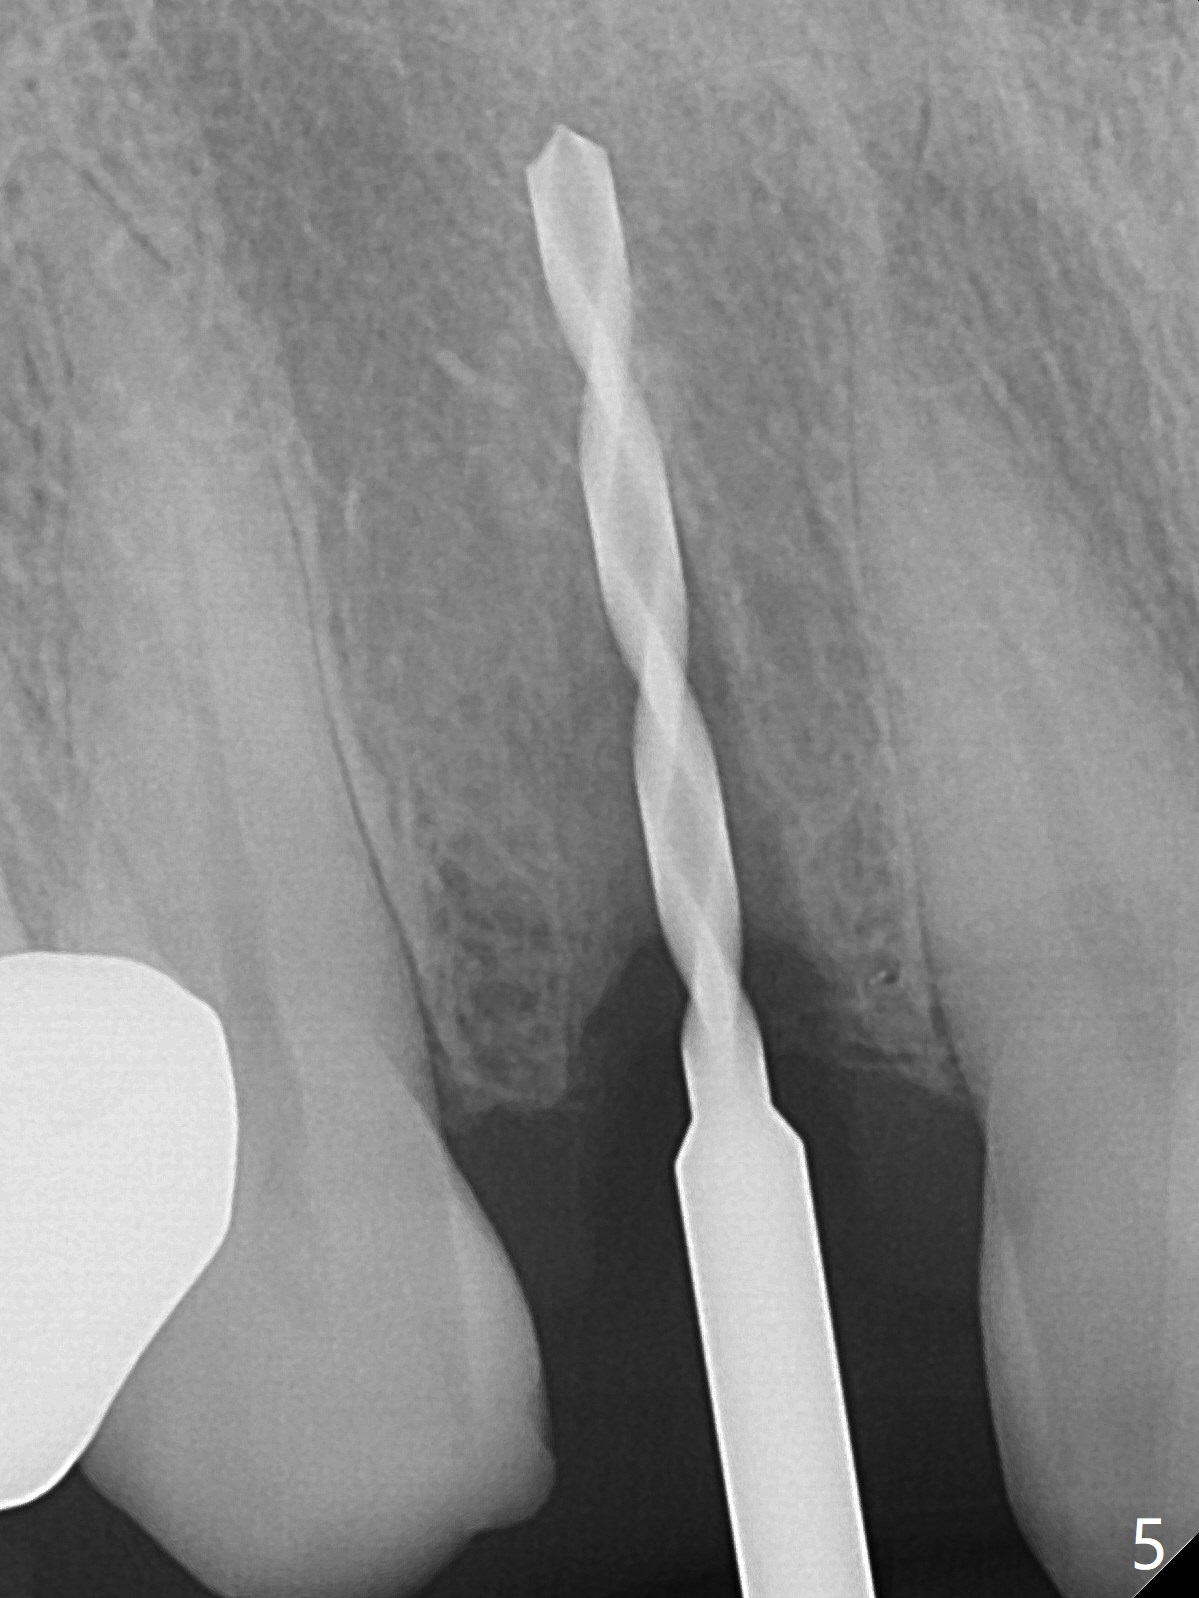

The rebonded crown at #7 debonds in a few days. There is deep anterior overbite and buccal concavity (Fig.1 *). The equigingival fracture (Fig.1,2) seems difficult to restore considering lack of posterior support (lower RPD in Fig.1). Buccal shield is tried in spite of the long root. It is not easy to tell whether the infected apex is removed due to the deep socket. In fact the apical buccal plate perforates because of use of surgical handpiece. Finally the buccal shied is removed. PA confirms the retained apex (Fig.3 *). The initial osteotomy with 1.5 mm drill in place is off trajectory (Fig.4). After adjustment of the trajectory of osteotomy (Fig.5), a 3x16(2) mm 1-piece implant is placed within normal limit (10-15 Ncm, Fig.6)). In fact bone graft is placed before (Fig.6,7 arrowhead; to repair apical buccal plate perforation) and after (Fig.6 *) implantation. The gingiva (including papillae) remains normal around the provisional 3 months postop (Fig.8). The bone graft becomes more organized 3 months postop (Fig.9), continues to do so 4.5 months postop (Fig.10) and becomes dense coronally 9 months post cementation (Fig.11: *).